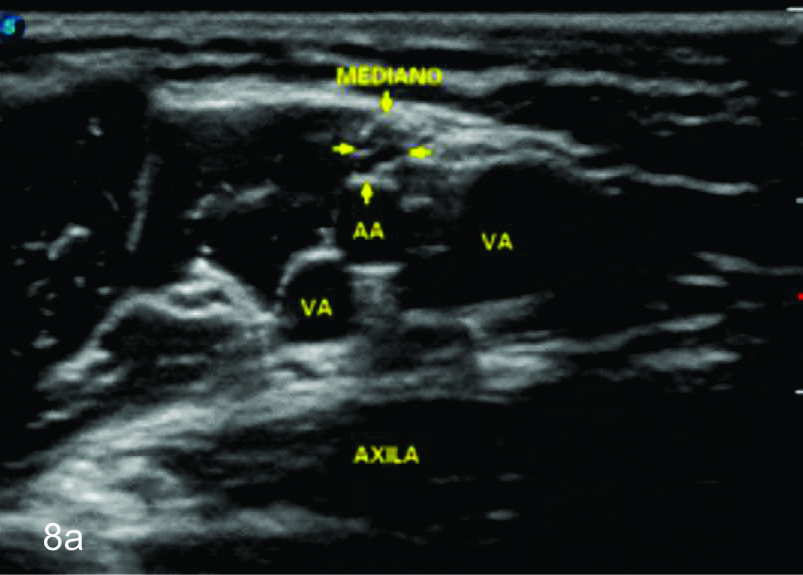

Figura 8

Nervio mediano

Serie de cortes axiales del nervio mediano desde su origen a nivel del hueco axilar hasta el sector distal del antebrazo previo a su ingreso al túnel del carpo. Se identifica el mismo señalado por flechas amarillas y con la palabra mediano. AA-arteria axilar, VA- vena axilar, AH- arteria humeral, VH- vena humeral, VB- vena basilar, AC- ateria cubital, VC- vena cubital, BA- músculo braquial anterior, PR- músculo pronador cuadrado, FS- músculo flexos superficial, FP- músculo flexor profundo, PC- músculo pronador cuadrado. A- axila, se identifica el nervio superfical a la arteria axilar, B- tercio medio del brazo en canal bicipital medial, lateral a la arteria humeral, C- codo, medial al tendón distal del bíceps braquial y a la arteria humeral luego de cruzarla, superficial al músculo braquial anterior, D-antebrazo sector cefálico, entre las dos cabezas del pronador redondo, E- tercio medio del antebrazo, entre los músculos flexor superficial y profundo F- tercio distal antebrazo, superficial al pronador cuadrado.